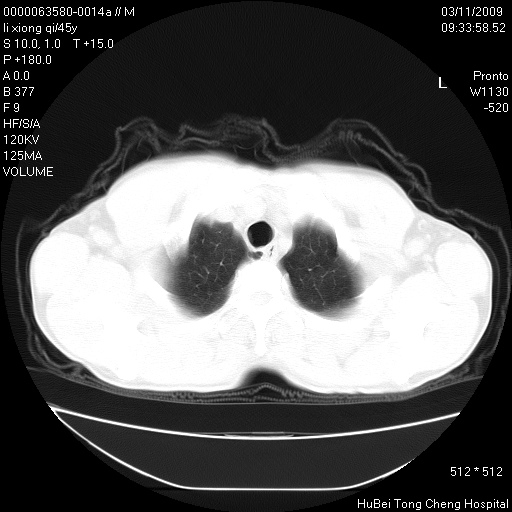

患者 男,45岁。胸痛,咳嗽伴痰中带血1月余。

临床诊断:肺结核?

胸部ct轴位平扫(层厚10mm,螺距1.5,重建间隔10mm),图像如下:

考虑肝癌肺转移